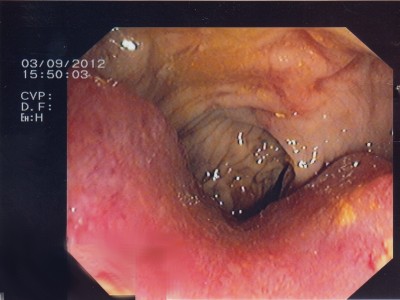

Abb. 2: Das Gebilde des oberen Mastdarmes, auch hier ist die Ent- fernung des Tumors mittels Darmspiegelung nicht mehr möglich. Abb. 2: Das Gebilde des oberen Mastdarmes, auch hier ist die Ent- fernung des Tumors mittels Darmspiegelung nicht mehr möglich.